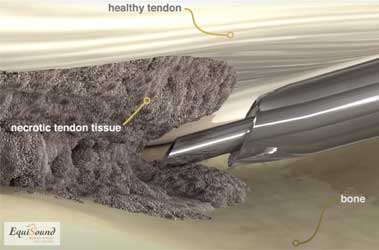

Chronische peesblessures bevatten frequent degeneratieve haarden en ontstaan door repetitieve overbelasting van een pathologische zone in de pees (tendinose) . Bij een tendinose bevat de pathologische haard verschillende soorten weefsel zoals fibreus-,fibrocartilagineus-, hyalien-, en/of beenderig weefsel. Deze haarden dragen niet bij aan de elastische functie van een gezonde pees en kunnen heel pijnlijk zijn. Ze fungeren zoals een "kiezel in een schoen": zij zijn blijvend pijnlijk en veroorzaken ook nieuwe ontstekingshaarden.

Een nieuwe evolutie in de chirurgie van pezen is het gebruik van Tenex: Ultrasound-guided Ultrasonic Tissue Debridement.

De TENEX techniek

Tenex is een behandelingstechniek die 5j geleden ontwikkeld werd in USA om chronische peesaandoeningen te behandelen bij mensen (chronische achillespezen, hielspoor, patellapeesdegeneratie etc). De techniek maakt gebruik van ultrason geluid (zoals bij het verwijderen van tandsteen) om beschadigd weefsel af te breken en zo het genezingsproces te stimuleren en een nieuwe herstelkans te geven. De geluidsfrequentie is specifiek gekozen om enkel harde weefsels (fibrose en mineralisaties) af te breken en geen schade aan te brengen aan gezond peesweefsel. De ultrason behandeling wordt toegediend door middel van een holle naald in een holle buis (zie foto 9a). Uit de holle naald komt tijdens de behandeling een influx van NaCl dewelke tegelijk geaspireerd wordt door de holle buis (foto 9b en 9c). Het water zorgt in eerste instantie voor de afvoer van gedebrideerd weefsel, maar tegelijk ook voor afkoeling van de naald dewelke erg opwarmt door het ultrason proces.

Doordat de naald echogeleid ingebracht wordt via steekincisies in de huid, is deze behandeling minimaal-invasief. Zo recupereert de patiënt sneller en is er weinig wondzorg nodig. Ook zorgt dit voor een exacte plaatsing van de naald in het degeneratieve gebied van de pathologische structuur.